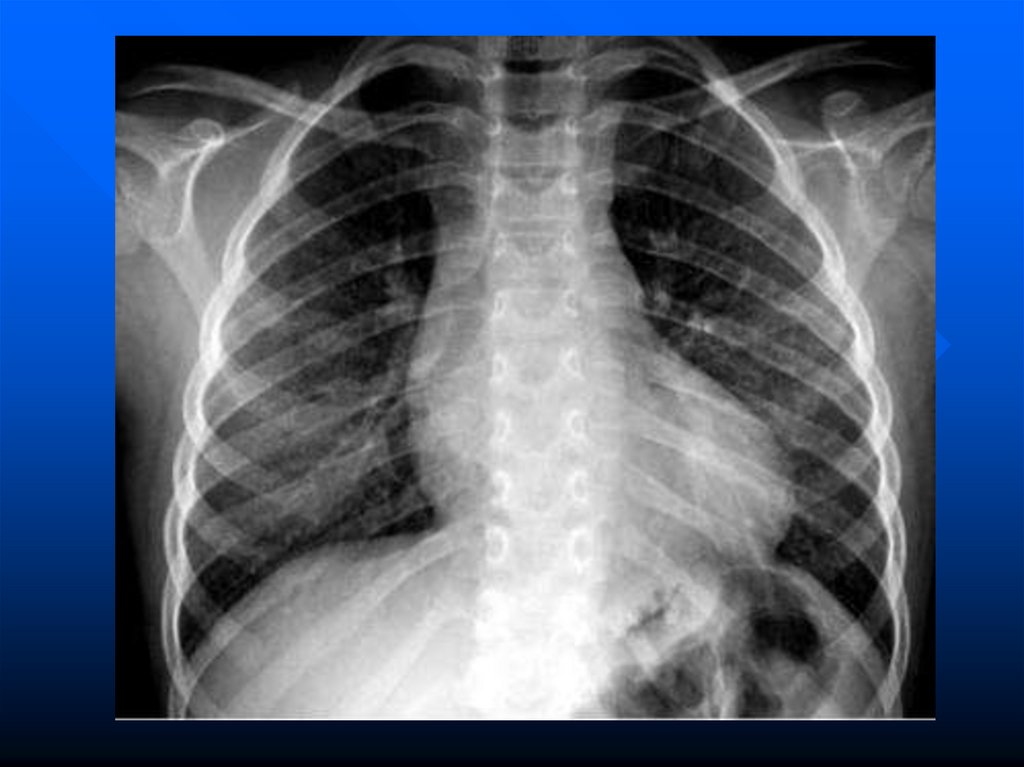

перегородок

формируется